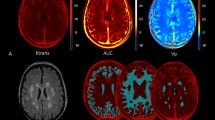

Following preprocessing, DWI data were fitted voxel-wise by nonlinear least squares using the lsqcurvefit module in Matlab to the intravoxel incoherent motion (IVIM) model43 describing the fractional change in signal: S/S0 = (1-vbw)*exp(-bD) + vbw*exp(-b(D + D*)), where b is the b-value for diffusion weighting, vbw is the volume fraction of blood, D is the bulk tissue diffusion coefficient and D* is the pseudodiffusion coefficient representing flow through ramified microvessels. The model generated, for each subject, voxel-wise maps of the three IVIM parameters, vbw, D, and D*, and the product vbw x D*, related to flow. The processed DWI data were also re-gridded in SPM12 to 2 × 2x4 mm resolution for registration and analysis with the pCASL data.

The first analysis of IVIM parameters focused on WMH manually delineated using the T2-FLAIR images and checked by the neuroradiologist (LW). Total WMH was calculated according to this segmentation. We assessed each IVIM parameter: the blood volume fraction, vbw, the bulk diffusion, D, the pseudodiffusion, D*, and the product vbw x D*, proportional to flow, voxel-wise throughout white matter segregated between regions of WMH, 4 mm thick peri-WMH zones, and remaining normal-appearing white matter (NAWM) (see Fig. 1 for an example). Peri-WMH zones were defined by dilating the segmented WMH regions by one voxel. All analyses were restricted to white matter for each patient using the white matter segmentation from preprocessing in SPM12. Differences in mean IVIM parameter values were assessed between regions for each patient. The mean difference between each pair of regions was evaluated by one-sample t-test across patients. A p < 0.05 was considered statistically significant after correction for multiple comparisons using false discovery rate.